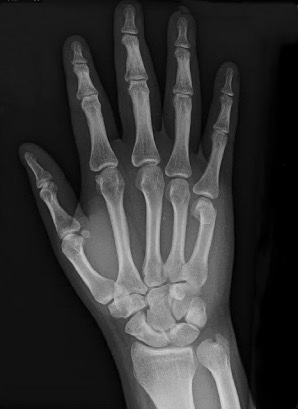

What’s the Diagnosis? Gepost op 31 augustus 201731 augustus 2017 door netwerkvsseh What’s the Diagnosis? @emdaily.cooperhealth.org Dit delen: Delen op X (Opent in een nieuw venster) X Share op Facebook (Opent in een nieuw venster) Facebook Delen op LinkedIn (Opent in een nieuw venster) LinkedIn E-mail een link naar een vriend (Opent in een nieuw venster) E-mail Afdrukken (Opent in een nieuw venster) Print Vind-ik-leuk Aan het laden... Gerelateerd